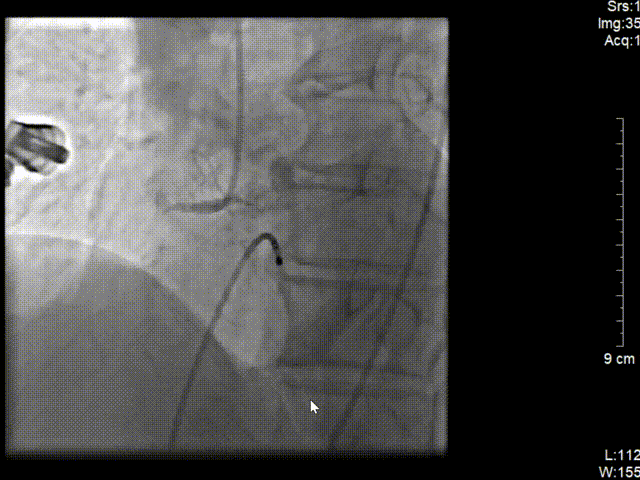

冠脉造影结果(右冠近段病变)

冠脉三支病变 右冠近端完全闭塞病变。

左图:6F JR4.0指引导管造影。

右图:右冠远段、近段各植入药物支架1枚。

在J型导丝指引下6F JR4.0指引导管于右冠口,行造影提示右冠近段急性闭塞,将SION blue导丝操作通过右冠近端闭塞处并达远段真腔,予2.0*15预扩张球囊行病变处预扩张处理,复查造影可见血栓,予血栓抽吸导管反复抽吸,抽出大量红色血栓。

再次予2.0*15预扩张球囊行病变处预扩张处理,右冠近中置入3.5*40mm药物支架1枚,继续予以3.5*15m后扩张球囊行支架内优化扩张。

复查造影可见右冠远段狭窄80%,并见血栓,予2.0*15预扩张球行右冠远段病变处预扩张,于右冠远段置入2.5*14mm 药物支架1枚,并予以3.0*12mm后扩张球囊行支架内扩张优化。再次造影示右冠狭窄消失,无夹层及残余狭窄,TIMI血流3级。